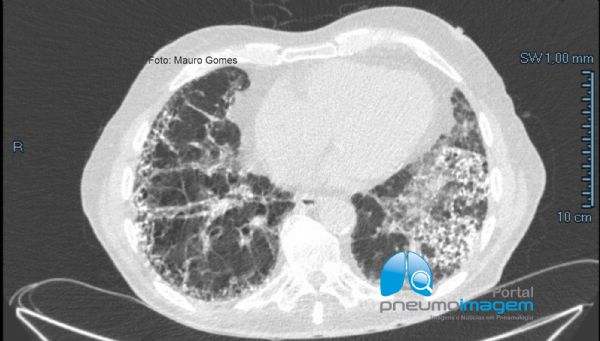

Nos cortes com a janela para o mediastino é possível se observar melhor os focos de calcificação intersticial.

In CT slices with the window to the mediastinum, it is possible to better observe the foci of interstitial calcification.